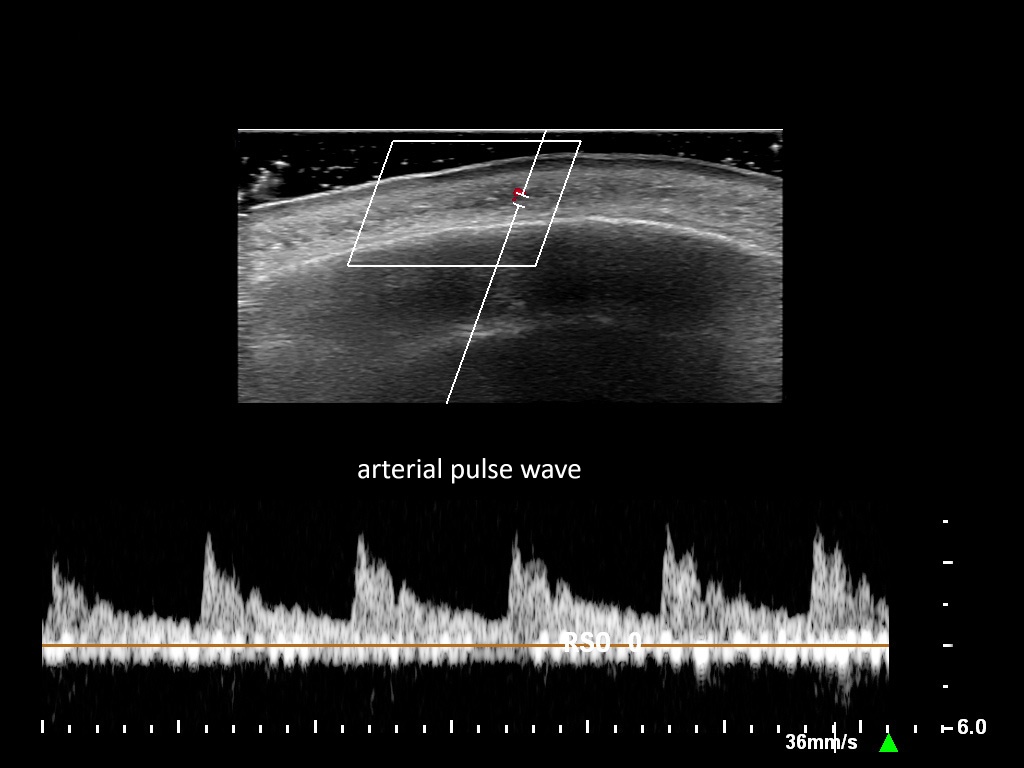

In this section you will learn more about the different layers of the face with the use of ultrasound. When you click on the secondary ultrasound image, you will see the different structures as an overlay. This will help to train yourself to recognize the different layers of the face.

Study the first image to recognize the different layers. If you are sure about the layers, swipe to the second image to view the answer (if applicable).